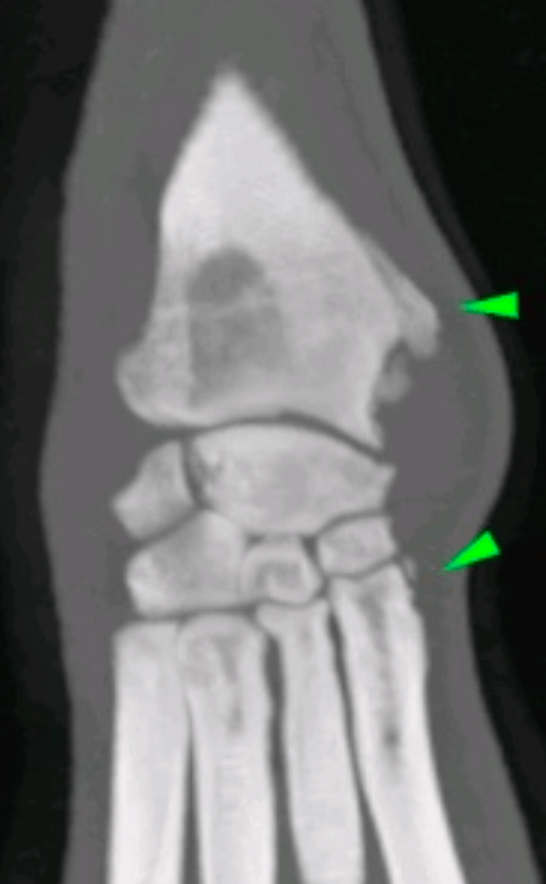

Un diagnostic précis repose sur une combinaison d’examen clinique et d’imagerie. Les radiographies et le scanner permettent de visualiser un gonflement des tissus mous et, dans certains cas, une prolifération osseuse sur la face médiale du radius distal. La ténosynovite du LAP peut être bilatérale, rendant l’examen des deux membres essentiel.

Scanner: Tuméfaction des tissus mous et prolifération osseuse sur la face médiale du radius distal.